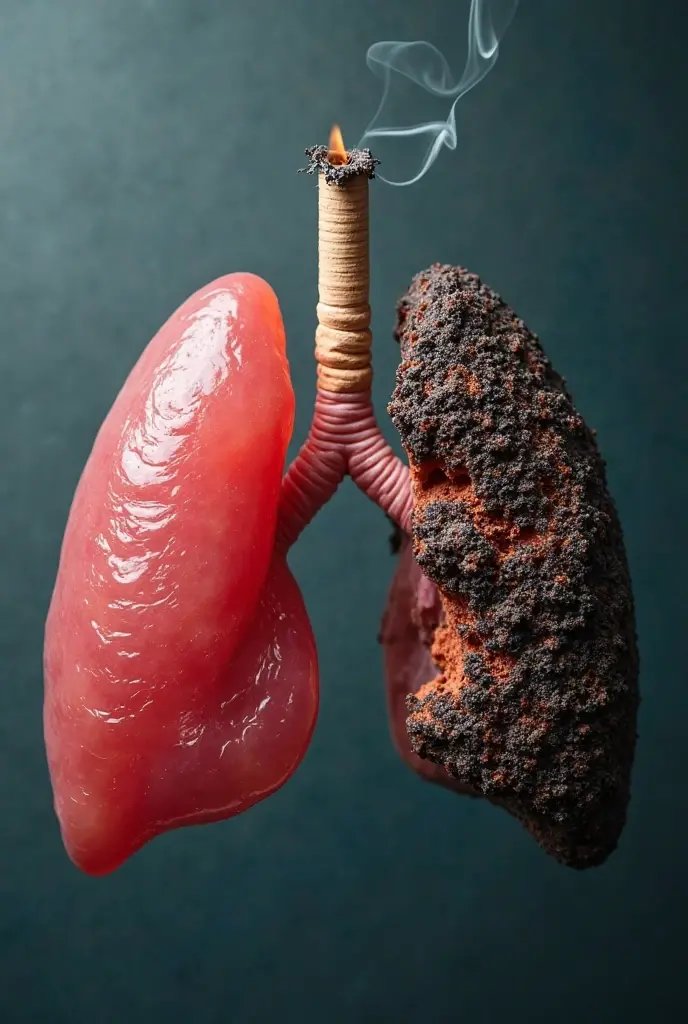

Generate a lungs, the right side lungs is healthy vibrant color surrounded with

Generate a lungs, the right side lungs is healthy vibrant color surrounded with fresh air. On the left side make the lungs damage or pollution of elements in smoking. Add some symbols of no smoking in the pulution part, and add some clean air in the right side lungs

Generate a lungs

the right side lungs is healthy vibrant color surrounded with fresh air

On the left side make the lungs damage or pollution of elements in smoking

Add some symbols of no smoking in the pulution part

and add some clean air in the right side lungs